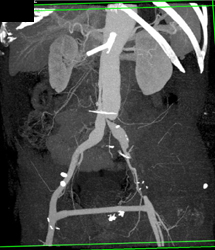

Aortic Dissection